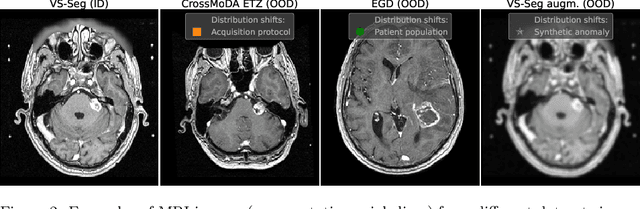

Abstract:Deep Learning models perform unreliably when the data comes from a distribution different from the training one. In critical applications such as medical imaging, out-of-distribution (OOD) detection methods help to identify such data samples, preventing erroneous predictions. In this paper, we further investigate the OOD detection effectiveness when applied to 3D medical image segmentation. We design several OOD challenges representing clinically occurring cases and show that none of these methods achieve acceptable performance. Methods not dedicated to segmentation severely fail to perform in the designed setups; their best mean false positive rate at 95% true positive rate (FPR) is 0.59. Segmentation-dedicated ones still achieve suboptimal performance, with the best mean FPR of 0.31 (lower is better). To indicate this suboptimality, we develop a simple method called Intensity Histogram Features (IHF), which performs comparable or better in the same challenges, with a mean FPR of 0.25. Our findings highlight the limitations of the existing OOD detection methods on 3D medical images and present a promising avenue for improving them. To facilitate research in this area, we release the designed challenges as a publicly available benchmark and formulate practical criteria to test the OOD detection generalization beyond the suggested benchmark. We also propose IHF as a solid baseline to contest the emerging methods.

Abstract:Deep Learning (DL) models tend to perform poorly when the data comes from a distribution different from the training one. In critical applications such as medical imaging, out-of-distribution (OOD) detection helps to identify such data samples, increasing the model's reliability. Recent works have developed DL-based OOD detection that achieves promising results on 2D medical images. However, scaling most of these approaches on 3D images is computationally intractable. Furthermore, the current 3D solutions struggle to achieve acceptable results in detecting even synthetic OOD samples. Such limited performance might indicate that DL often inefficiently embeds large volumetric images. We argue that using the intensity histogram of the original CT or MRI scan as embedding is descriptive enough to run OOD detection. Therefore, we propose a histogram-based method that requires no DL and achieves almost perfect results in this domain. Our proposal is supported two-fold. We evaluate the performance on the publicly available datasets, where our method scores 1.0 AUROC in most setups. And we score second in the Medical Out-of-Distribution challenge without fine-tuning and exploiting task-specific knowledge. Carefully discussing the limitations, we conclude that our method solves the sample-level OOD detection on 3D medical images in the current setting.